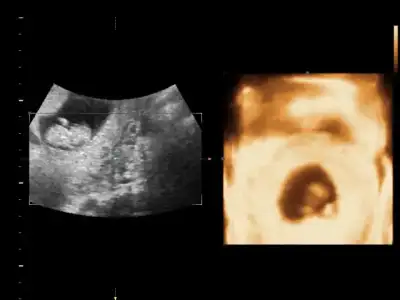

ben nub göremedim. yani anlamadım fotodan

Bu bebek durusu degisik geldi goremedim bisey canim

Bacakları açık aslında hiç çıkıntı yok gibiBu bebek durusu degisik geldi goremedim bisey canim